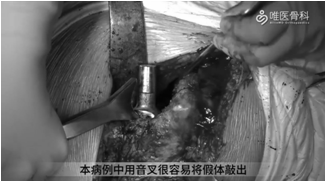

取出股骨假体:用骨刀去除假体近端周围的覆盖骨,使假体颈领充分显露,再用薄骨刀将假体与骨水泥界面进行分离。然后采用股骨假体专用工具取出假体,本病例采用音叉很容易就将假体取出。